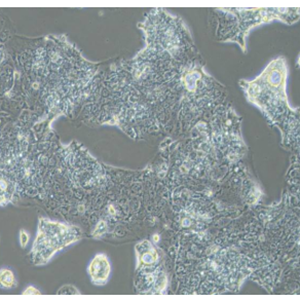

SW1463(人大肠癌细胞)